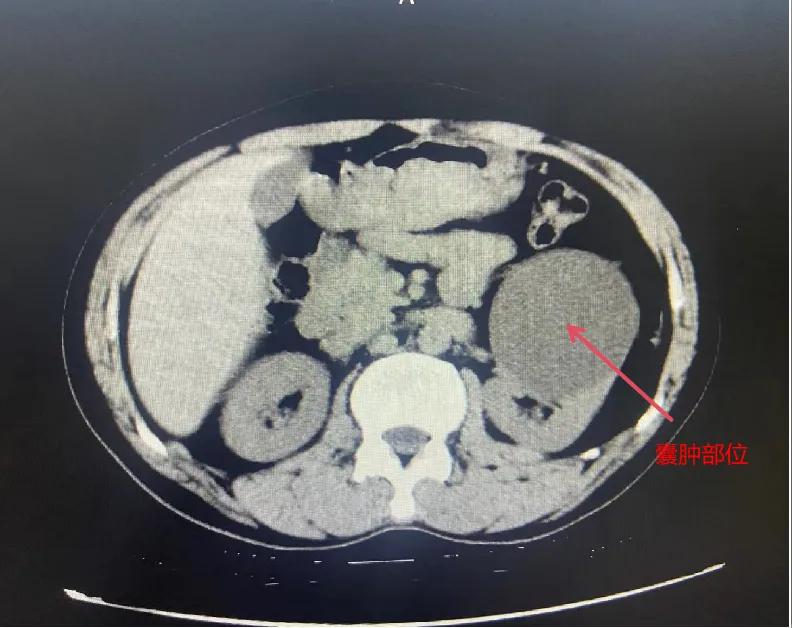

漯河市骨科醫(yī)院泌尿外科開展后腹腔鏡下腎囊腫去頂減壓術(shù)

近日,漯河市骨科醫(yī)院(漯河醫(yī)專二附院、漯河市立醫(yī)院)連續(xù)收治2例腎囊腫患者。泌尿外科主任閆衛(wèi)甫和副主任醫(yī)師王金柱等醫(yī)師團(tuán)隊(duì)經(jīng)討論研究后,決定為患者采取后腹腔鏡下腎囊腫去頂減壓術(shù),經(jīng)過(guò)手術(shù)室、麻醉科等科室大力配合成功完成手術(shù)。

閆衛(wèi)甫表示,后腹腔鏡技術(shù)是一種微創(chuàng)外科手術(shù)方法,它通過(guò)在后腹腔(即腹膜后的空間)建立一個(gè)手術(shù)空間,利用腹腔鏡器械進(jìn)行手術(shù)操作。這種技術(shù)特別適用于泌尿系統(tǒng)等后腹腔臟器的手術(shù)。與傳統(tǒng)手術(shù)相比具有創(chuàng)傷小、恢復(fù)快、并發(fā)癥少、視野清晰等優(yōu)點(diǎn)。與前腹腔鏡相比則具有對(duì)腹腔臟器干擾較少的優(yōu)點(diǎn)。目前,后腹腔鏡手術(shù)主要用于腎囊腫去頂減壓術(shù)、腎上腺腫瘤切除、早期腎癌根治術(shù)、腎腫瘤剜除術(shù)等。

腎囊腫是一種常見的腎臟良性疾病,其發(fā)病率逐年增加。近年來(lái)隨著腹腔鏡技術(shù)的迅速發(fā)展,后腹腔鏡下腎囊腫去頂減壓術(shù)成為治療腎囊腫的主要方法。該手術(shù)具有創(chuàng)傷小,手術(shù)時(shí)間短,術(shù)中出血少,術(shù)后康復(fù)快,出院時(shí)間短等優(yōu)點(diǎn),并且術(shù)后復(fù)發(fā)率低,被認(rèn)為是治療腎囊腫的理想術(shù)式。(盧 闖 聶方方 劉 旭 袁錦鈺)